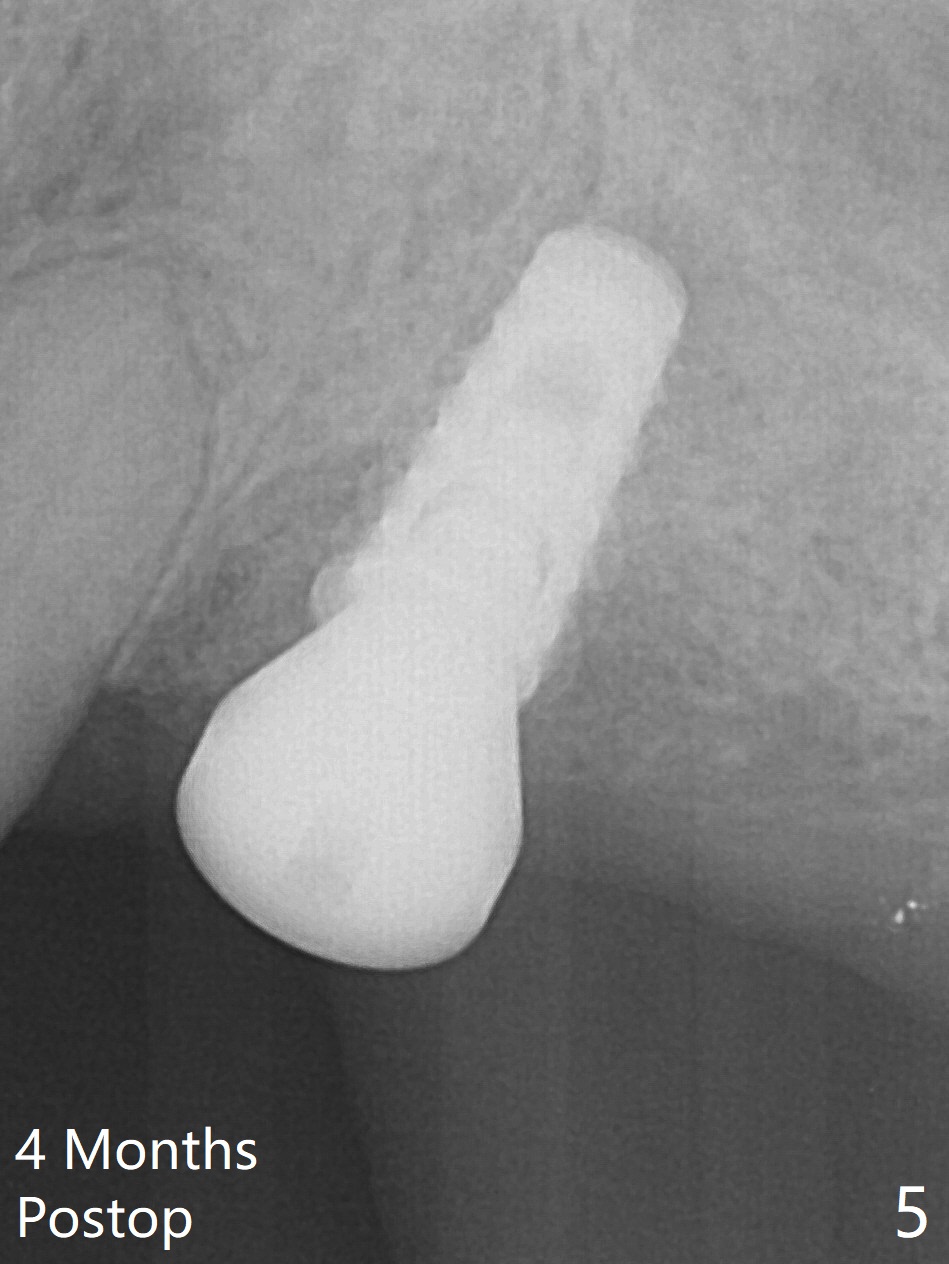

After extraction of the tooth #14 (Fig.1) and removal of granulation tissue associated with a distal fistula, a 1.6 mm drill is used to initiate osteotomy in the septum for 9 mm, followed by insertion of a 7 mm long parallel pin (Fig.2).  The length of the subsequential osteotomy is 11 mm until 4.8 mm in diameter (overprep as will be shown below).  The bone is hard so that sinus lift fails with 4.8 mm Magic Expander.  Since a 5x9 mm dummy implant is placed with stability, a definitive implant with the same dimension is chosen with >50 Ncm (Fig.3,4).  Prior to and after abutment placement, Vera graft is placed (*).  The provisional perforates with loose abutment 3.5 months postop.  A 6x4 mm healing abutment is placed.  Osteointegration occurs 4 months postop (Fig.5,6).